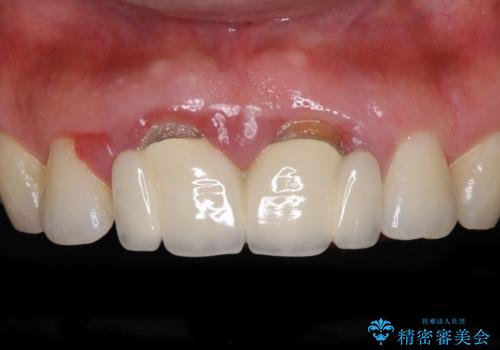

- [ 再生治療・歯周外科・小矯正・セラミック補綴 ] 前歯の歯周病治療- 担当医 大元洋佑 ![[ 再生治療・歯周外科・小矯正・セラミック補綴 ]  前歯の歯周病治療の症例 治療前](https://seimitsushinbi.jp/wp/wp-content/uploads/2022/12/83065c2454a29ed71cf190e15a6106f4-500x350.jpg?v=1671673398) ![[ 再生治療・歯周外科・小矯正・セラミック補綴 ]  前歯の歯周病治療の症例 治療後](https://seimitsushinbi.jp/wp/wp-content/uploads/2022/12/ec16e37ee53325a6f6629b94759f5513-500x350.jpg?v=1671673454)